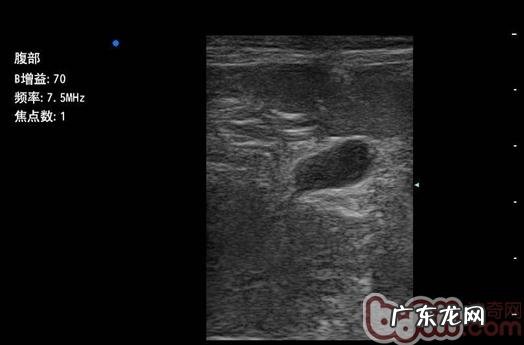

B超查验

B超查验:膀光骨间可探及杂带样构造 , 直徑1.5-2cm , 腔内呈无回音至低回声反射面;肾脏功能尾侧可探及低回声卵圆型构造 , 长短约1.4-1.5厘米 。

膀光壁变厚 , 腔内可探及高回音光斑反射面 。